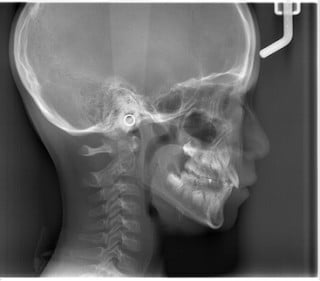

パノラマ(お口全体のレントゲン)・セファロ(お顔・手のレントゲン)・口腔内写真(現在の歯並びの写真)・顔写真・歯の型取り

をして丁寧に状態の確認を行います。

セファロ

上下のあごの大きさ/上下のあごのズレ/あごの形/歯の傾斜角/口元のバランス など

成長発育の段階を確認

手の骨(足の骨)は成長に合わせて形、大きさを変えていくことが分かっています。成長の段階を知ることで、治療開始時期の決定や使用装置の効果を予測。